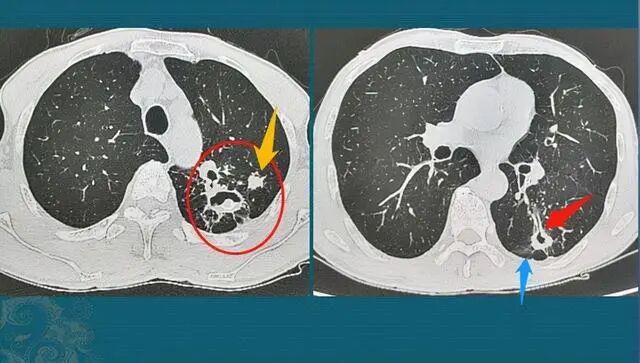

与此同时,尸检报告与药物检测的结果也陆续出来。原来,这七名女生皆死于甲拌磷中毒,而甲拌磷是一种剧毒的农药,毒性极大,仅需2毫克便可让一个活生生的人在短时间内死亡。

服用甲拌磷的中毒者会接连出现呼吸衰竭、肺水肿等症状,这个痛苦的过程将持续十几分钟。